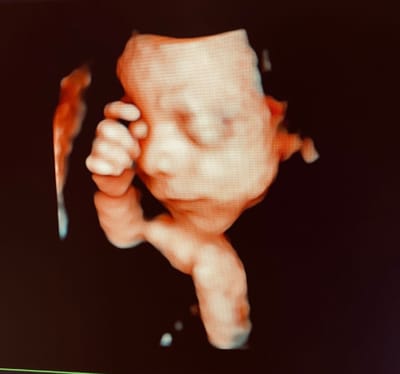

Ecografia 3 D e 4D. Alcuni ecografi, grazie a particolari sonde, hanno la possibilità di effettuare ecografie tridimensionali (3D) e quadridimensionali (4D). Queste ecografie, oltre a trovare sempre più impiego in ginecologia ed ostetricia per facilitare la diagnosi di varie patologie (spina bifida, alcune patologie del sistema nervoso e cardiache fetali, malformazioni uterine, etc.), vengono da anni utilizzate per far conoscere ai futuri genitori loro figlio. La visualizzazione del feto in 3D e 4D consente di iniziare già durante la gravidanza il rapporto affettivo e relazionale con il proprio bambino. Le immagini tridimensionali sono ferme ed è possibile vedere il feto da varie prospettive, mentre l’ecografia 4D da la possibilità di osservare le immagini tridimensionali in movimento. Per ottenere delle buone immagini è necessario che il feto sia posizionato adeguatamente, che ci sia una buona quantità di liquido amniotico e che la futura mamma non pesi troppo (il tessuto adiposo non lascia passare gli ultrasuoni adeguatamente).

Ecografia 3D e 4 D imageEcografia 3D e 4 D imageEcografia 3D e 4 D image